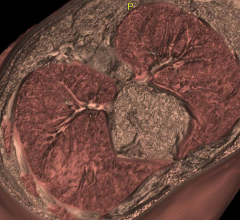

Feature | Computed Tomography (CT) | Dave Fornell

(More recent articles and videos on trends, advances and innovations in computed tomography systems can be found at the…

Over the past few years, iterative reconstruction has emerged as an alternative to filtered back projection with its…